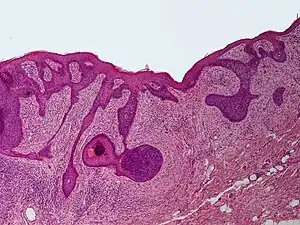

Perifollicular fibroma is a cutaneous condition, a benign tumor usually skin colored, most often affecting the face and upper trunk.[1]: 674 [2]

Concentric layers of cellular fibrous tissue around hair follicles representing perifollicular fibroma